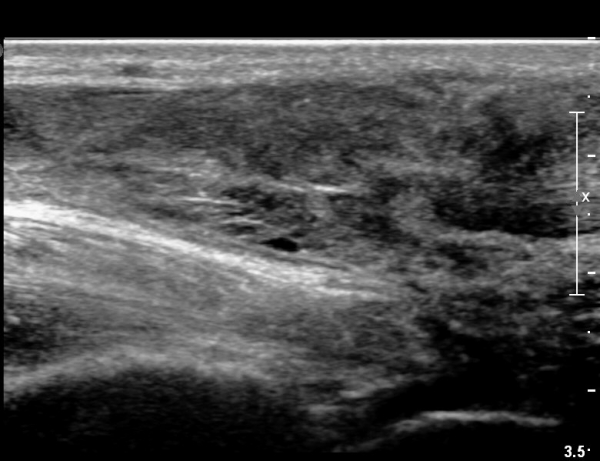

³»Ãø ºñº¹±Ù Á¾´Ü¸é°Ë»ç¿¡¼­ ³»Ãø ¹èº¹±Ù ¸»´ÜºÎ ÆÄ¿­°ú °¡Àڹ̱٠½ÉºÎ¿¡ ¼ö¾×Àú·ù°¡ °üÂûµÊ(»çÁø 1, 2).

¾ÆÅ³·¹½º°Ç Á¾´Ü¸é°Ë»ç¿¡¼­ ¾ÆÅ³·¹½º°Ç ¸»´ÜºÎ¿¡ ¾ÆÅ³·¹½º°ÇÀÇ Àú¿¡ÄÚºÎÁ¾, ±¹¼ÒÀû ¿¬°á¼º ¼Ò½Ç,

¹ß¸ñ°üÀý ÈĹæºÎ¿¡ ¼ö¾×Àú·ù°¡ °üÂûµÊ(»çÁø 3, 4, 5).